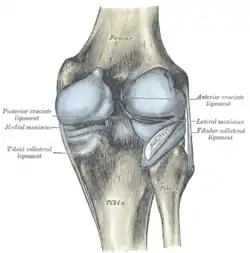

Cruciate ligaments

Left knee-joint from behind, showing interior ligaments.